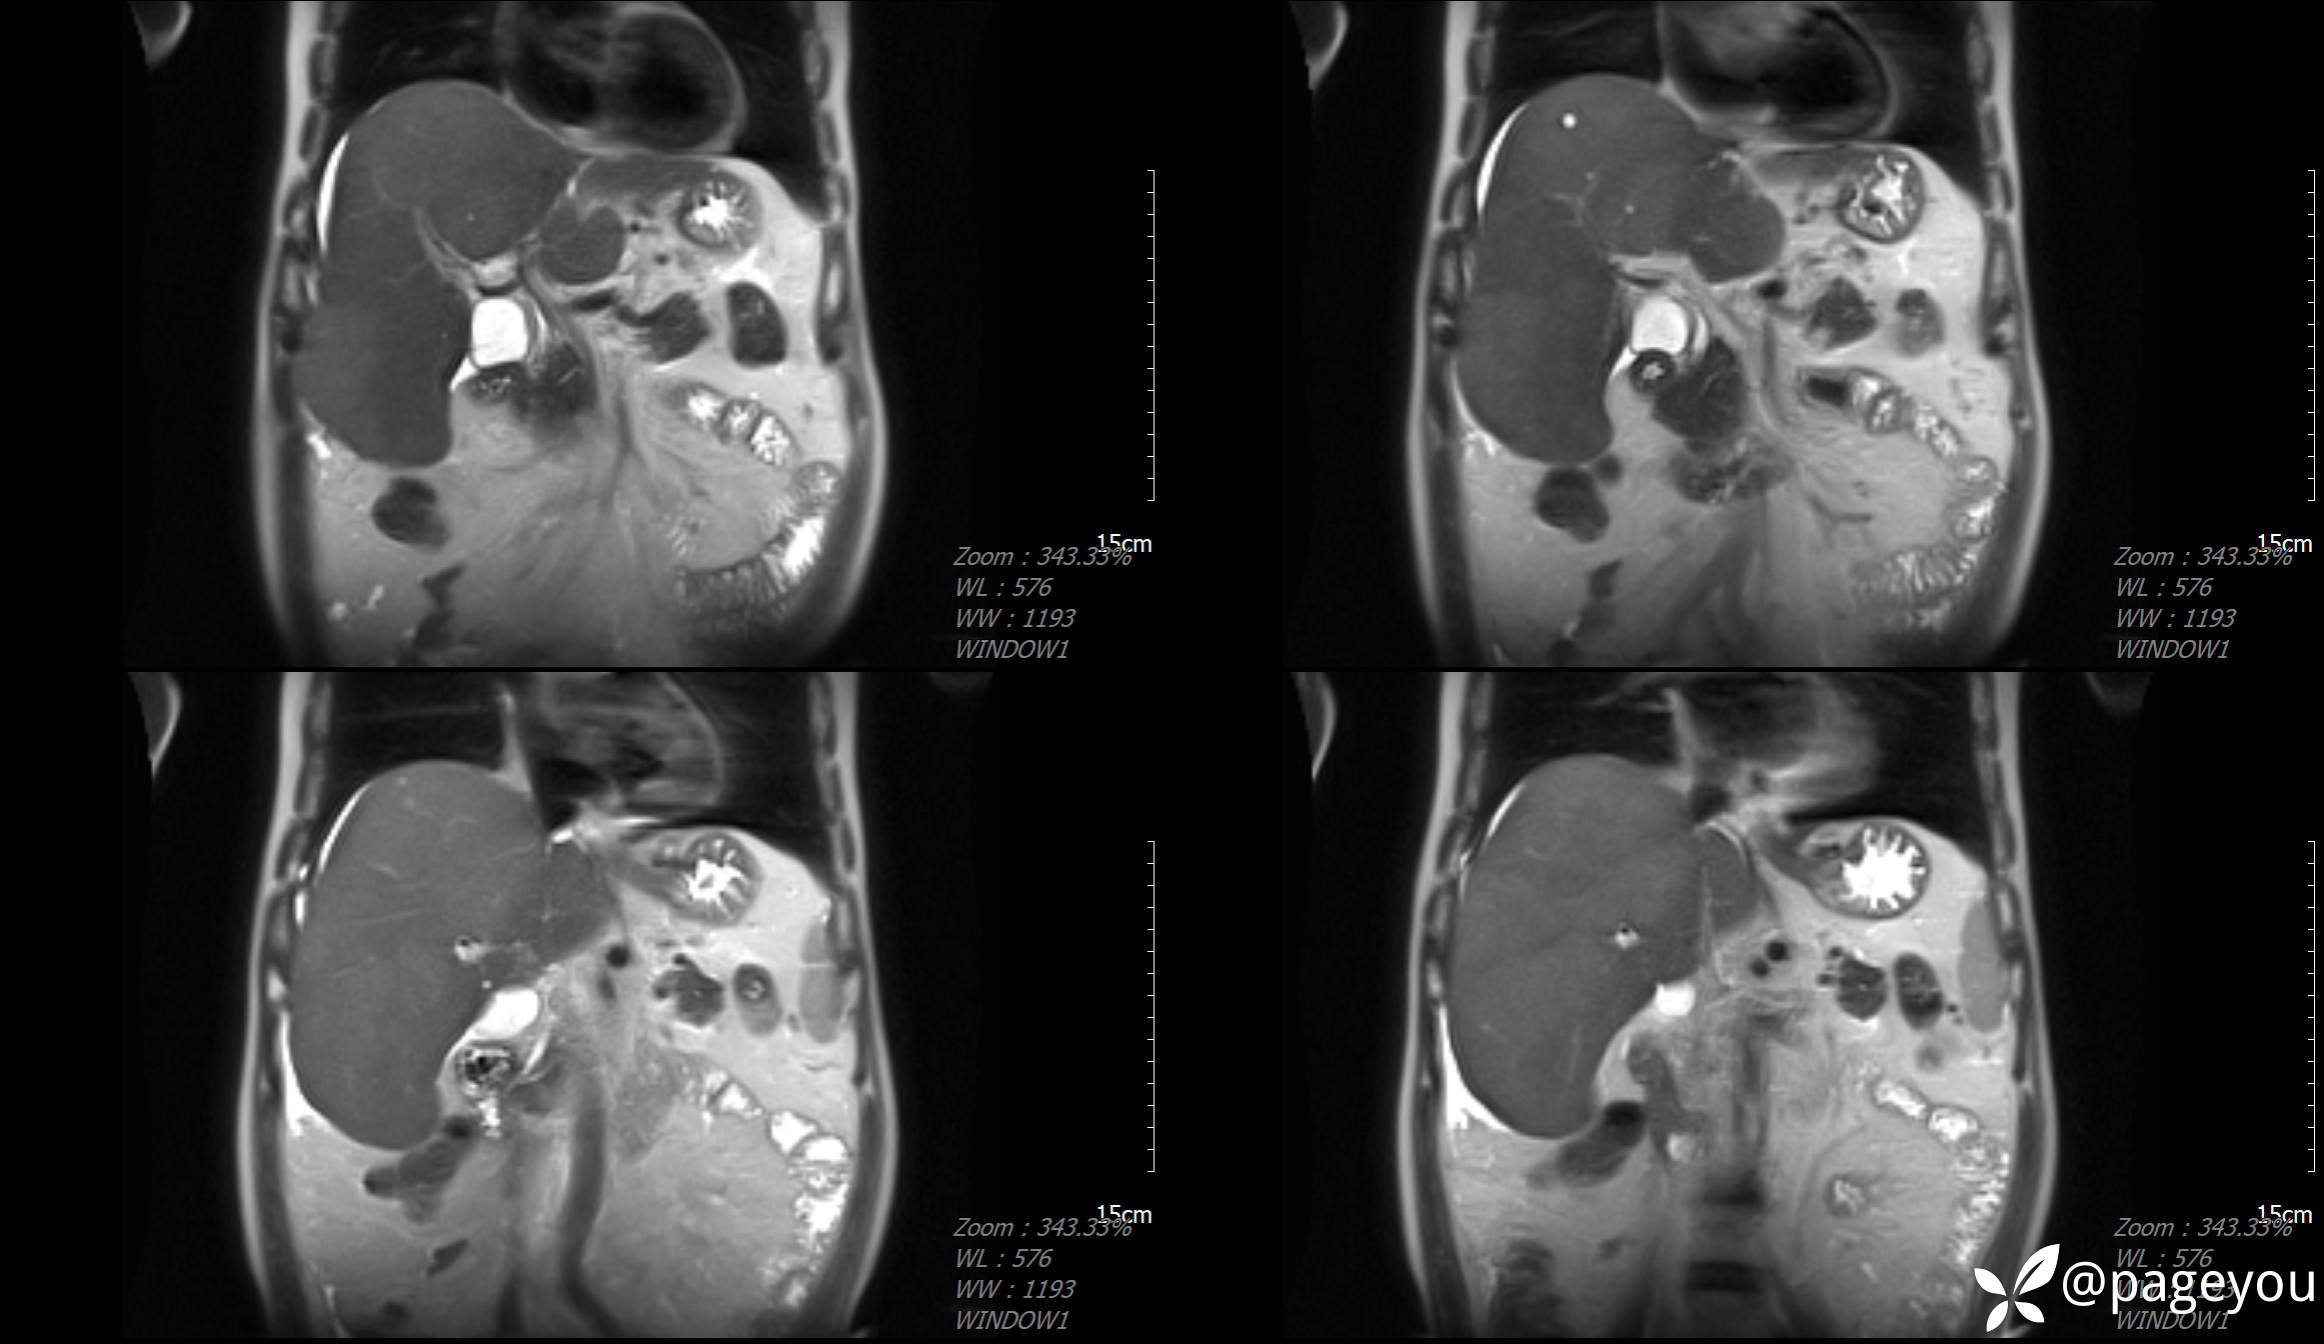

MRI检查: